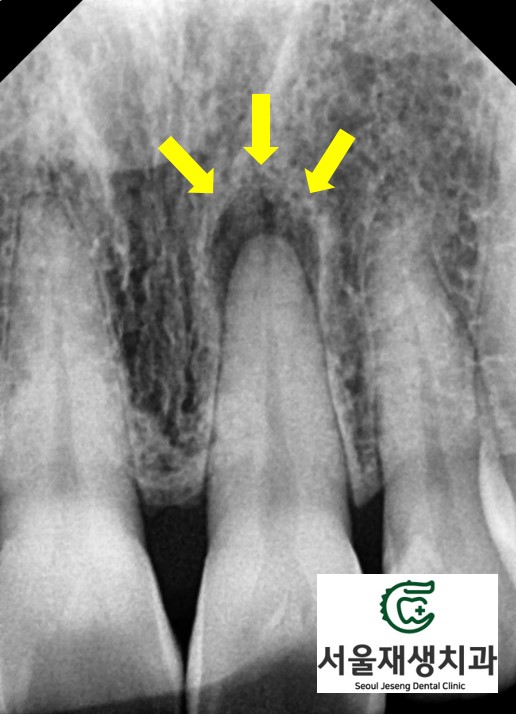

엑스레이를 보면 알 수 있습니다.

치아 뿌리 끝에 달린 까만 주머니가 보이시나요?

외상 혹은 반복적인 습관 (젓가락 씹기, 손톱 물어뜯기)으로 인해,

치아 내의 신경이 손상되어

결국 괴사에 이르게 되었다는 뜻입니다.

치아 내부에 남은 괴사 조직은

대개 검붉은 색을 띄고,

겉으로 보기에는

짙은 오렌지색, 회색, 갈색 등으로

비쳐보이게 됩니다.